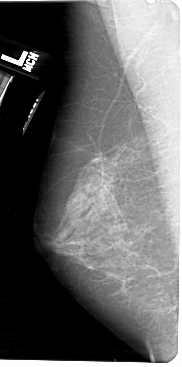

A_1520_1.LEFT_MLO

LEFT_MLO LINES 5491 PIXELS_PER_LINE 2716 BITS_PER_PIXEL 12 RESOLUTION 43.5 NON_OVERLAY